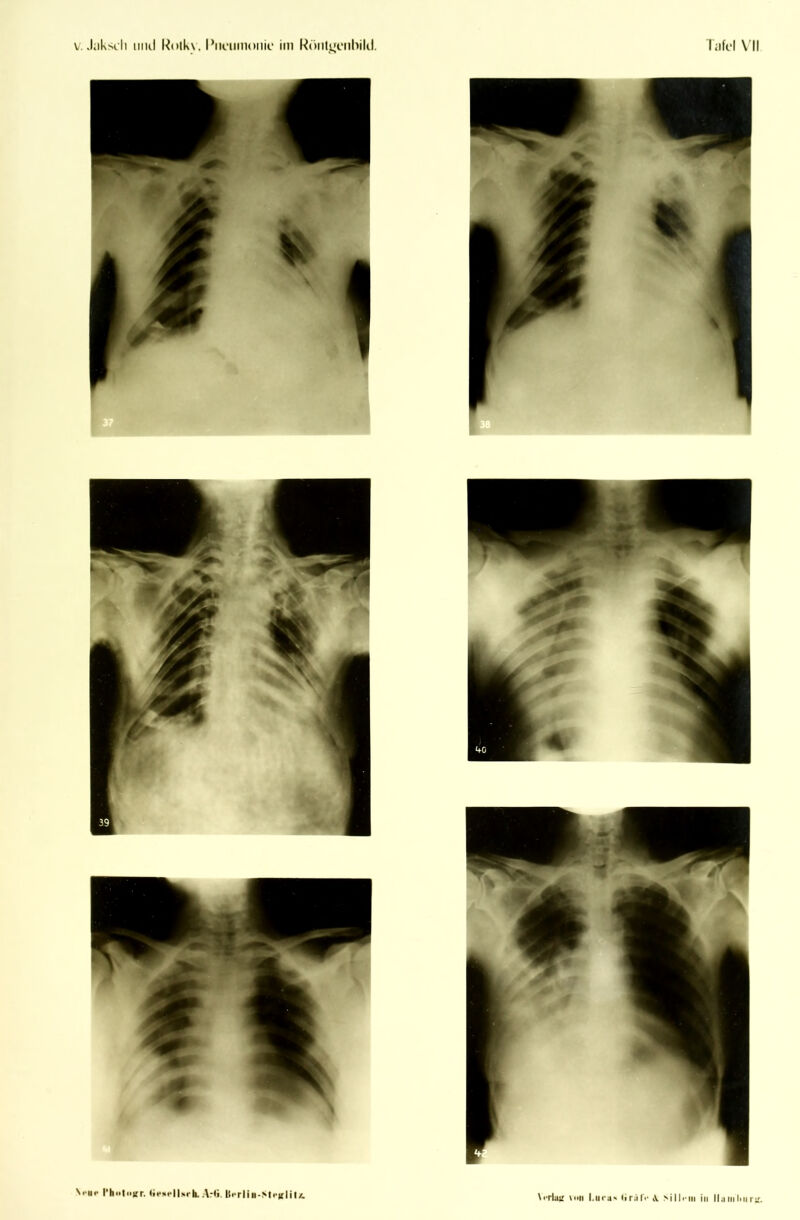

Die Pneumonie im Röntgenbilde ... : mit 59 Röntgenbildern auf 10 Tafeln und 10 Skizzenblättern / von R.v. Jaksch und H. Rotky.

Credit: Die Pneumonie im Röntgenbilde ... : mit 59 Röntgenbildern auf 10 Tafeln und 10 Skizzenblättern / von R.v. Jaksch und H. Rotky. Source: Wellcome Collection.